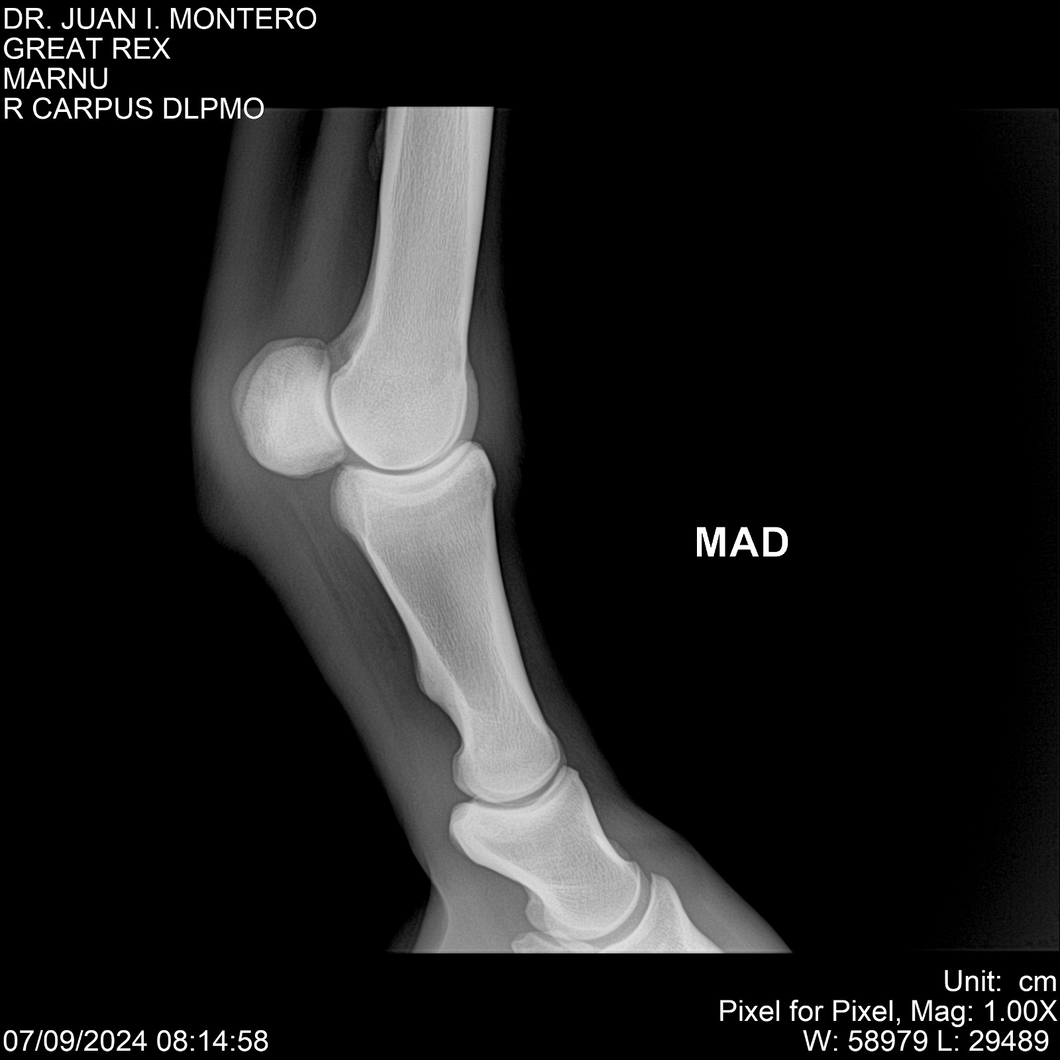

LOTE 4, GREAT REX Lote Anterior Volver al remate Lote Siguiente Ficha Contacto Montevideo - Ficha del Lote Identificador: #282518 Categoría: Yeguarizos Montevideo - 66 Visualizaciones ClicData Contacto Empresa: Abelenda N. R., Walter Hugo Nombre*: Teléfono* : E-mail* : Mensaje Enviar Registrese gratis Este contenido Exclusivo está disponible sólo para usuarios registrados Ingresar